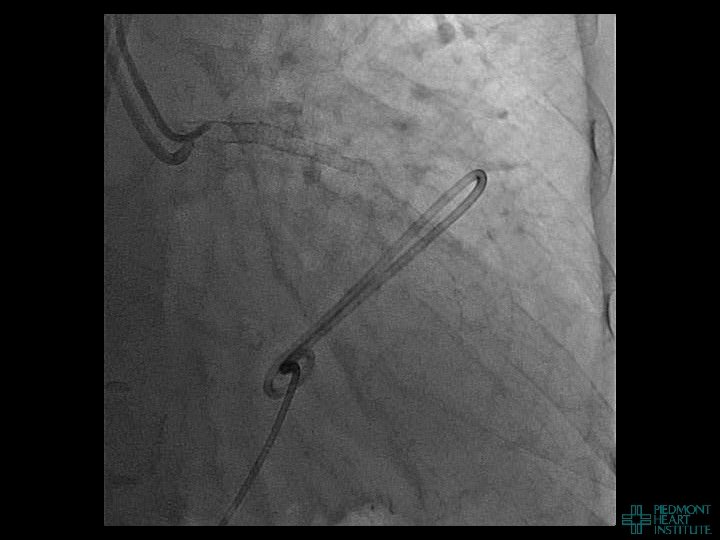

Case Example 4